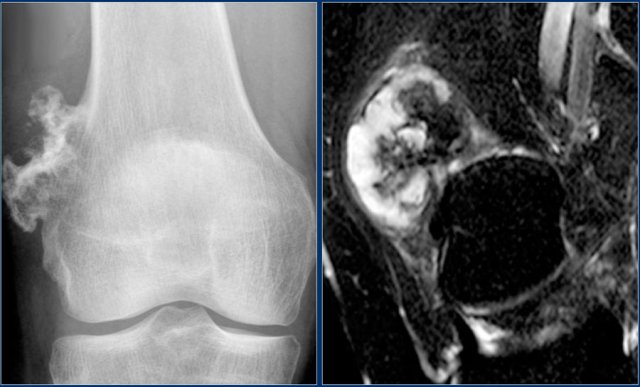

Here a patient with a broad-based osteochondroma.

Notice that the cortical bone extends into the lesion.

This feature differentiates it from a juxtacortical tumor.

Here a patient with a broad-based osteochondroma with extension of the cortical bone into the stalk of the lesion.

Notice the lytic peripheral part with subtle calcifications.

This part corresponds to a zone of high SI on T2-WI with FS on the right.

This represents a thick cartilage cap.

This is an example of progression of an osteochondroma to a peripheral chondrosarcoma.